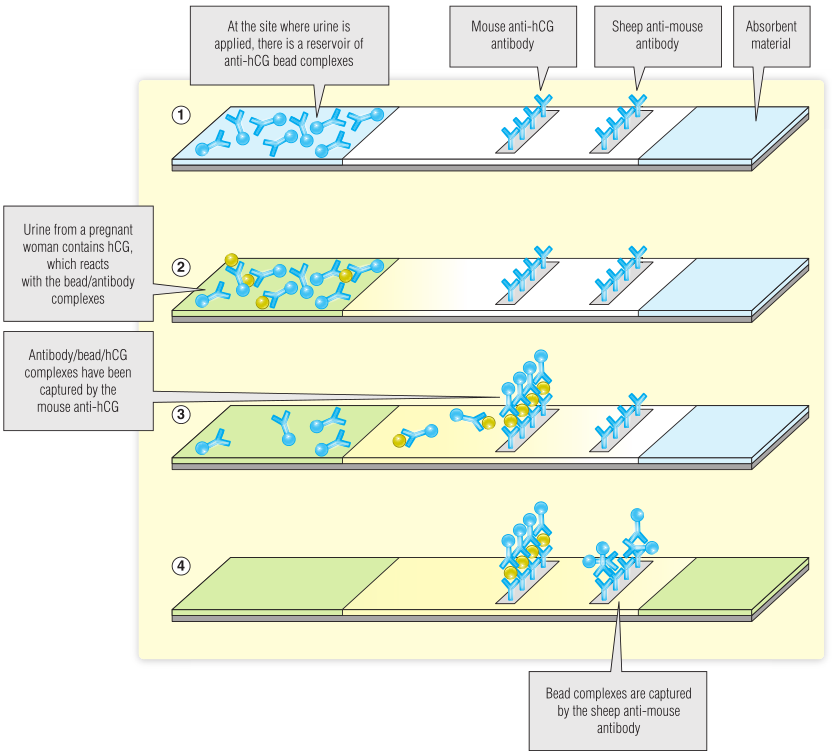

侧向流动试验

侧向流动试验是一种确定体液中是否存在蛋白质、抗原或抗体的简单测试。它与ELISA检测有一些相似之处,但经过精心设计,使用起来非常简单,不需要任何特殊设备,而且相对便宜。广泛使用在妊娠试验,它确认孕妇尿液中是否存在人绒毛膜促性腺激素(HCG)。

验孕棒是由一种具有吸收性的纸质材料制成的。放置在试棒一端的尿样将通过毛细管作用被吸引,并在沿试条的过程中遇到不同的试剂(Fig 5.4)。第一种试剂是与抗hCG表位的彩色微珠相连的小鼠抗体,当尿液第一次滴在验孕棒上时与之混合,如果有hCG存在,尿液就成为hCG-抗体-微珠复合物的一部分。虽然这些都是分散的,但这些复合体仍然是看不见的,并继续沿验孕棒流动。

Fig 5.4 妊娠棒检测呈阳性的事件顺序

接下来,尿液抗体混合物到达一个区域,在该区域,针对不同hCG表位的第二抗体已经固定在纸上。该抗体将结合并捕获任何hCG-抗体-珠状复合物。如果有足够的hCG,珠粒聚集的地方会形成一条彩色的线条。

怀孕测试需要包括一个对照,以表明测试情况令人满意。例如,必须确保尿液沿着验孕棒流动,以及抗体珠复合物的存在。在这个例子中,尿液接下来会遇到羊体内产生的第三种抗体的区域,该抗体是针对小鼠免疫球蛋白的。这将捕获最后几个珠子,并将产生一条控制线,表示测试成功。

Fig 5.5显示了怀孕测试的阳性和阴性结果,以及未通过的检测(例如,当使用的尿液不足时)。